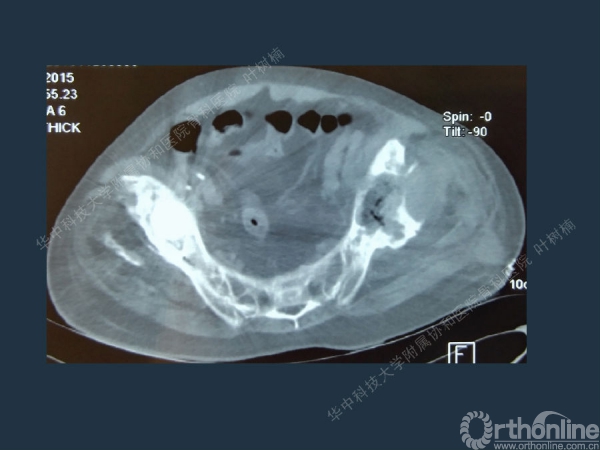

股骨侧翻修

髋臼缺损的处理